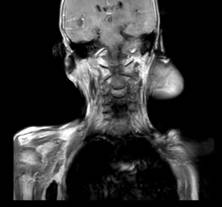

Hình ảnh bệnh nhân trước phẫu thuật

Cụ bà L.T.C nhập viện trong tình trạng có khối u lớn vùng mặt bên trái, gây đau, biến dạng khuôn mặt và ảnh hưởng nhiều đến sinh hoạt trong suốt nhiều năm. Kết quả sinh thiết xác định đây là ung thư biểu mô tế bào đáy dạng tuyến nang (adenoid type) - một thể hiếm gặp của ung thư da.